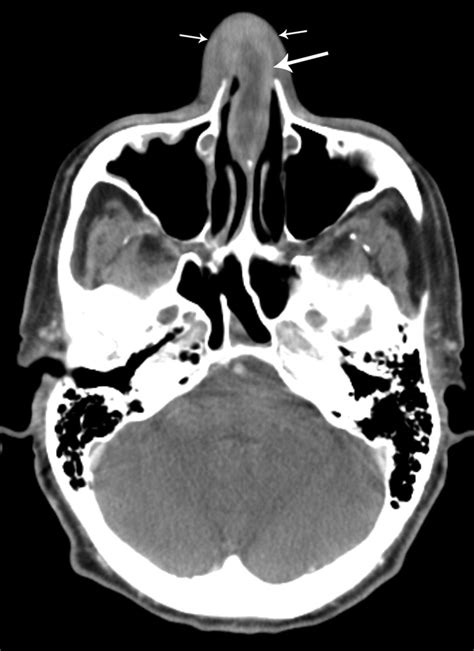

Nasal Septal Haematoma

A Nasal Septal Haematoma is a medical condition that requires immediate attention and prompt intervention. It occurs when blood collects within the space between the cartilaginous or bony septum—the wall separating the two nostrils—and the overlying mucous membrane, known as the perichondrium or periosteum. While often resulting from trauma to the nose, such as a sports injury, fall, or physical altercation, this condition must never be ignored. If left untreated, the accumulation of blood can block the blood supply to the septal cartilage, leading to its death and potential permanent structural deformity of the nose, commonly referred to as a "saddle nose" deformity.

Upon arriving at an emergency department or an ENT (Ear, Nose, and Throat) specialist's office, the physician will perform a thorough physical examination. This typically involves the use of a nasal speculum and a light source to inspect the interior of the nasal cavity. If a Nasal Septal Haematoma is suspected, the doctor may gently touch the swollen area with a probe. A haematoma will typically feel soft, boggy, and fluctuant, as opposed to a hardened fracture or simple edema.